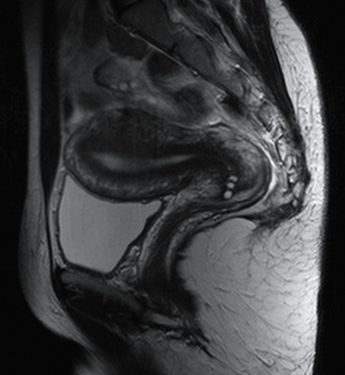

RM Pelvis

Prueba diagnóstica no invasiva que consiste en la obtención de imágenes de alta definición anatómica de la pelvis mediante el empleo de un campo electromagnético y ondas de radio (con un emisor y un receptor). No utiliza radiación ionizante. Se realiza para estudiar patologías del útero, del ovario, de las trompas y la vagina, ya sean de origen tumoral, inflamatorio o vascular. Esta prueba permite valorar órganos como la vejiga urinaria, la unión entre los uréteres y la vejiga, la próstata, las vesículas seminales, la uretra, los huesos de la pelvis, etc A veces requiere el uso de contraste intravenoso (Gadolinio) para caracterizar las lesiones.